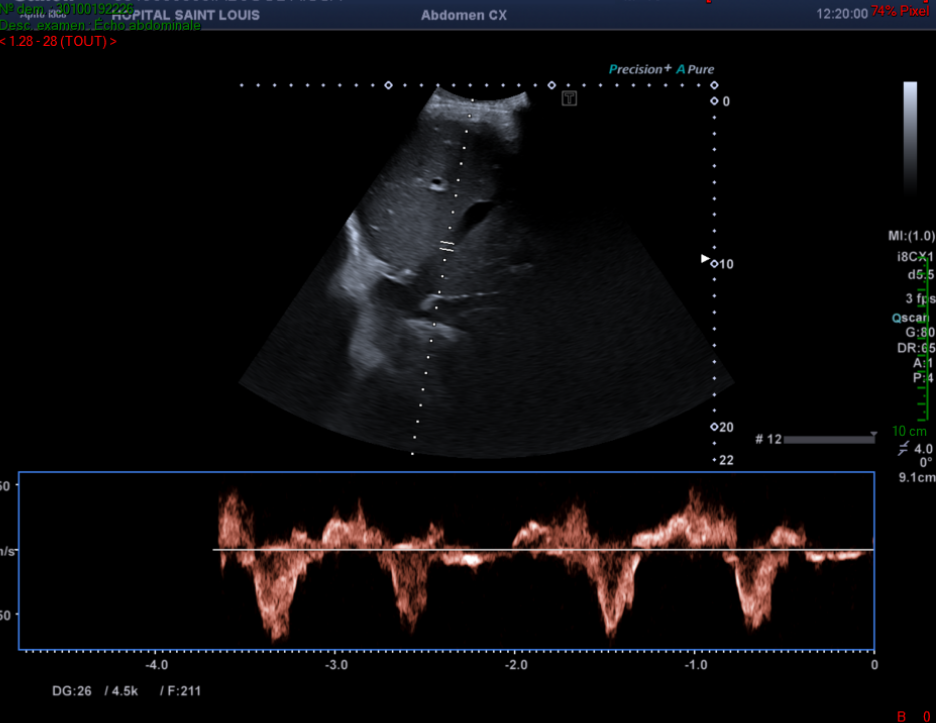

Il observe alors une alternance entre un flux hépatopète et hépatofuge au sein du tronc porte.

Un flux portal normal est dirigé vers le foie (hépatopète).

Un spectre normal du tronc porte est continu avec une légère pulsatilité liée à la décélération lors de l’inspiration.

Une importante pulsatilité est évocatrice d’une dysfonction ventriculaire droite et/ou d’une importante insuffisance tricuspide, signe indirect d’une hypertension artérielle pulmonaire.